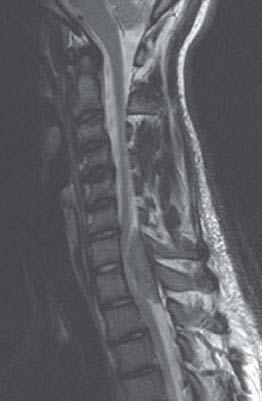

15. A 69-year-old man presents with 6 months of gradually progressive lower extremity weakness. His MRI is shown in Figure 11.3. Regarding this patient’s condition, which of the following is correct?

FIGURE 11.3 Sagittal T2-weighted MRI

The patient’s history and MRI shown in Figure 11.3 are consistent with a cervical spondylotic myelopathy with spinal cord compression, which has occurred slowly over months. This condition is the most common cause of spinal cord compression in the elderly. Spondylosis is a degeneration of the spinal column, in which there is formation of osteophytes that eventually lead to compression of the spinal cord and nerve roots. Along with this, there are also disc herniations and ligamentum flavum hypertrophy, leading to narrowing of the spinal canal. Because the degenerative process progresses slowly, the neurologic manifestations develop insidiously, unlike acute cord compressions in which the patient has manifestations of spinal shock, which include weakness below the level of the lesion with flaccidity and hyporeflexia, sensory loss, and sphincteric dysfunction.

Patients with cervical spondylotic myelopathy gradually develop neck stiffness and pain, weakness at and below the compression level, and unsteady gait. The examination shows findings of upper motor neuron signs below the level of compression, with spastic paraparesis, hyperreflexia, and upgoing toes. In the upper extremities there may be evidence of lower motor neuron signs, such as areflexia and atrophy, mainly at the same level of the compression. Patients have sensory deficits and may experience L’hermitte’s phenomenon, an electric sensation radiating down the back that occurs following neck flexion. The diagnostic test of choice is MRI of the spine. Goals of treatment include prevention of further neurologic deficits and therapies to help improve existing ones. Surgical decompression is the treatment of choice. Nonoperative options may provide pain relief; however, once myelopathic findings are evident surgical intervention may be required.

Radiation therapy plays no role in the treatment of cervical spondylotic myelopathy, and is reserved for the treatment of radiosensitive neoplasms. Steroid therapy is not indicated and is mainly used in patients with traumatic spinal injury and in neoplastic cord compression.